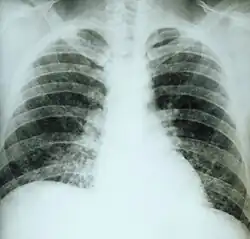

Primary pulmonary histoplasmosis

| This chest film shows diffuse pulmonary infiltration due to acute pulmonary histoplasmosis caused by H. capsulatum. | |

Primary pulmonary histoplasmosis is caused by inhalation of Histoplasma capsulatum spores, and approximately 10% of people with this acute infection develop erythema nodosum.[1]: 316